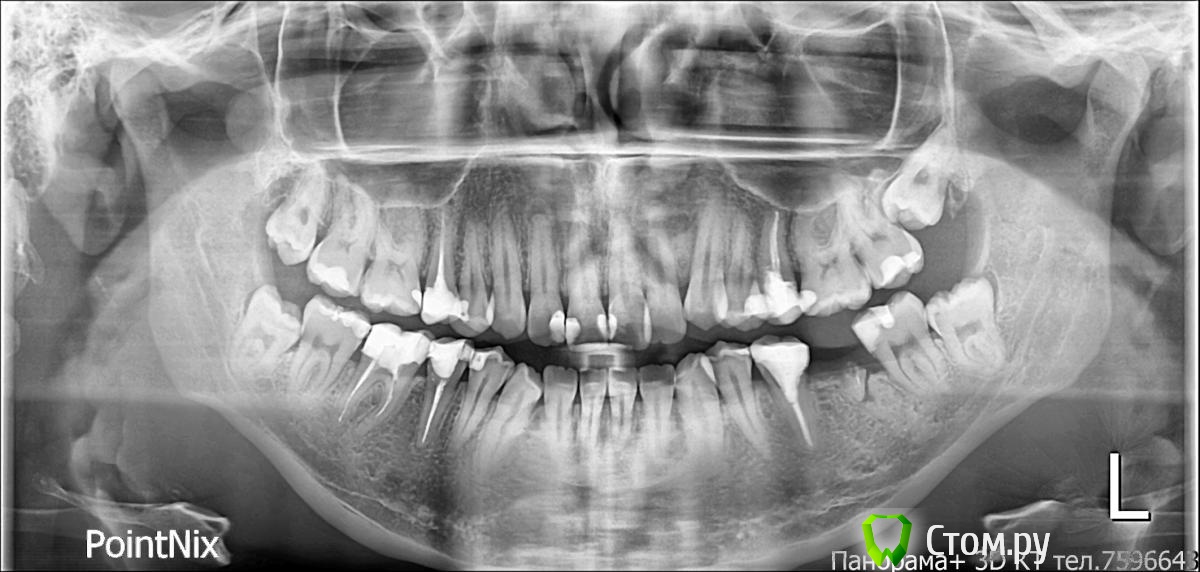

Викторовна575 Опубликовано 16 апреля, 2014 Поделиться Опубликовано 16 апреля, 2014 Когда был удален 36?если давно,навряд ли удастся переместить 37 без мезиального наклона.Я бы удалила все 8-ки,на место 36-имплантат или мост Ссылка на комментарий

LeFor Опубликовано 16 апреля, 2014 Поделиться Опубликовано 16 апреля, 2014 как показывал Попов, на семинаре по вектор тасам, не имеет значение давность удаления... на винтах все заезжает без всяких наклонов...зы: и 36 кстати до сих пор не удален) а вообще много терапии вначале.... 12 с "кистой", 47 нужно проверить, если все как на снимке, то все "плохо", в месте контакта с 48... 2 мм дефицита места дадут +6 к торку во фронте, сепарируете между клыком и четверкой по 0.7, итого 2-1.4=0.6мм это 1.5 градуса к торку- это незаметно, даже для нее...но если смотреть в рот более менее комплексно, и подумать о долгосрочной перспективе то, если оставить замученные 5ки вверху и 6ки внизу, то придется удалять целые 8ки!!! а судя по качеству терапии 5ки и 6ки долго не прослужат... вот поэтому лично я бы снес 5ки верх и 6ки низ... закрывать все с максимальной потерей(возможно даже со стабилизацией фронта на определенном этапе, но это как пойдет) и ставить 8ки нормально... Ссылка на комментарий

IgorH Опубликовано 17 апреля, 2014 Автор Поделиться Опубликовано 17 апреля, 2014 Мне ближе всего лечение с удалением вверху 5,и внизу 46,правда,я еще выбираю,убирать 46 или 45, в любом случае,оставшийся зуб планируем перелечивать,и качественно запломбировать канал Ссылка на комментарий

LeFor Опубликовано 17 апреля, 2014 Поделиться Опубликовано 17 апреля, 2014 в моих расчетах на вч дефицит места не 2 мм,а 11 мм,возможно я ошибся,я считал по моделям,мезио-дистальные размеры зубов,и место в зубном ряду с помошью нитки(знаю есть специальные графические методы) .а как Вы просчитываете деффецит места в зубном ряду? на глаз)) у меня же есть только фото... дефицит ну максимум 4мм... максимальная потеря,вы имеете ввиду анкораж? анкораж, на сколько я знаю переводится примерно как- опора... так что я имею ввиду наоборот, закрывать пространства с максимальной потерей опоры. я планирую на вч устанавливать Даемон с высоким торком,для стабилизации фронта или я ничего не понял, или... зачем высокий торк если вы боитесь протрузии? Мне ближе всего лечение с удалением вверху 5,и внизу 46,правда,я еще выбираю,убирать 46 или 45, в любом случае,оставшийся зуб планируем перелечивать,и качественно запломбировать канал только проверьте прежде 47... если там все обойдется, то лучше убрать 46, т.к. 45 лучше выглядит+ больше вероятности что его нормально пролечат+ симметричное лечение предсказуемее.. 1 Ссылка на комментарий